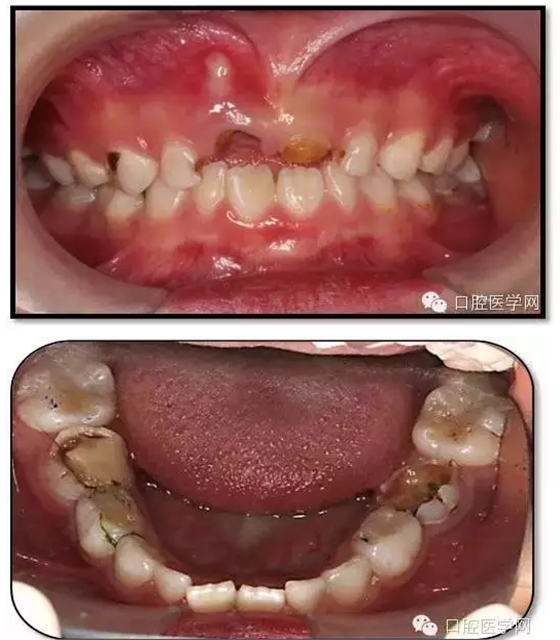

臨床檢查: 75OL齲洞, 舌側(cè)牙體完全劈裂斷端齊齦,探及大量軟化腐質(zhì)。頰側(cè)牙齦紅腫見瘺管,擠壓大量溢膿。叩(±),不松動(dòng)。X線:75根管空虛,牙根吸收約1/2,根尖周及根分歧大面積透射影,35發(fā)育4期,骨硬板尚連續(xù);51殘根,唇側(cè)牙齦瘺管,叩(±),不松動(dòng)。X線:51牙根吸收約1/2,根尖周低密度影。

85O、84DO充填體邊緣不密合,叩(±),不松動(dòng)。84頰側(cè)牙齦略紅腫。X線:84遠(yuǎn)中根及髓室底完全吸收,根分歧透射影,近中根內(nèi)側(cè)見外吸收,44上方骨硬板連續(xù)。85近中根完全吸收,髓室底吸收,根分岐透射影,遠(yuǎn)中根管內(nèi)見根充影像。45發(fā)育4期,骨硬板連續(xù)。

診斷: 75OL、51、85O、84DO慢性根尖炎

65OL、74O中齲 55OL、53DL深齲

16OL、26O、36OB、46OB窩溝淺齲